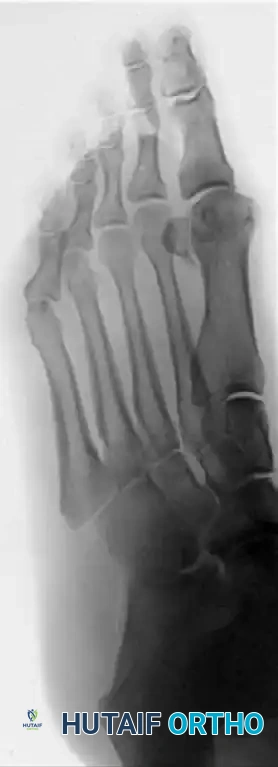

Patient with stage II hallux rigidus

Figure 1: Patient with stage II (radiographically) hallux rigidus; note the prominent dorsal osteophyte over the first metatarsal.